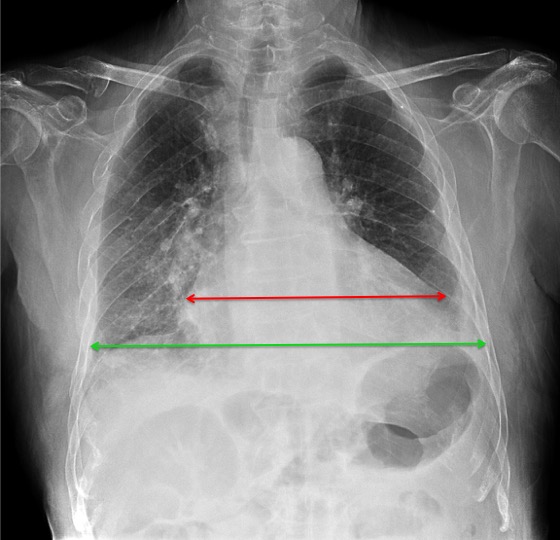

CASO: Paciente con insuficiencia cardiaca y antecedentes de traumatismo costal derecho.

Hallazgos:

- Fracturas costales hemitórax derecho con formación de callo.

- Cardiomegalia global con líquido en cisura y pequeño derrame pleural izquierdo en probable relación con fracaso cardíaco.

- Osteoporosis columna dorsal con disminución de altura del cuerpo vertebral de probable origen osteoporótico.

- Fractura tercio distal clavicular derecha con acabalgamiento de fragmentos.

Hay que valorar siempre el tamaño cardiaco. La relación cardiotorácica se obtiene realizando la división entra la longitua transverasal del corazón y el diámetro interno torácico mayor. Si es mayor a 0,5 se considera que existe cardiomegalia.